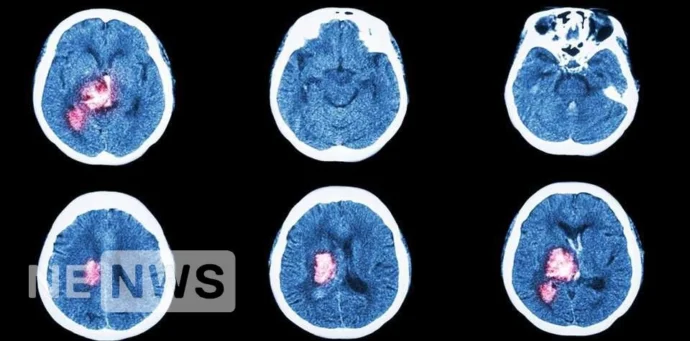

Ознаки інсульту іноді людина не відразу помічає, що з нею щось не так, або думає, що нездужання пройде саме. Через це втрачається дорогоцінний час. Тому важливо знати, як виглядає інсульт і що при ньому робити. Основні ознаки інсульту 1. Несподівано і сильн...